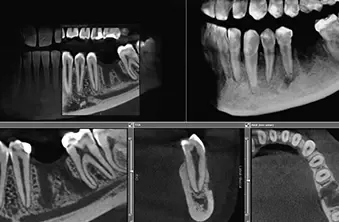

Imamo sodobno opremljeno zobozdravstveno ordinacijo, v kateri vam hitro, ugodno, predvsem pa kvalitetno nudimo peskanje zob. K nam v Ljubljano pa se naročite tudi, če potrebujete: